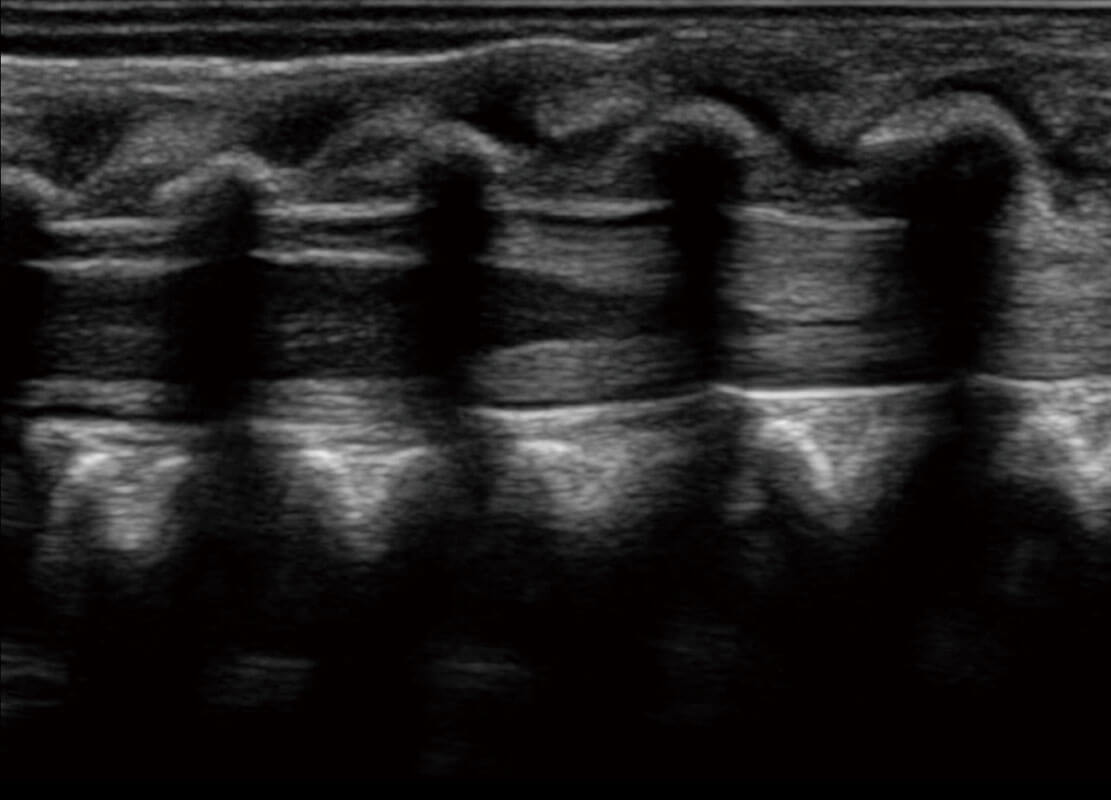

乳腺超声 / 新生儿

P60搭载宽频带线阵探头、宽景成像、弹性成像技术,为您提供乳腺应用方案。P60支持高频相控阵探头、线阵探头、腹部高频探头、腹部微凸探头等,丰富的探头群搭载敏感的彩色血流成像,适用于新生儿多种脏器检测要求,满足新生儿筛查需求。

• 新生儿肝血管癌

• 新生儿脊髓圆锥

• 新生儿心脏